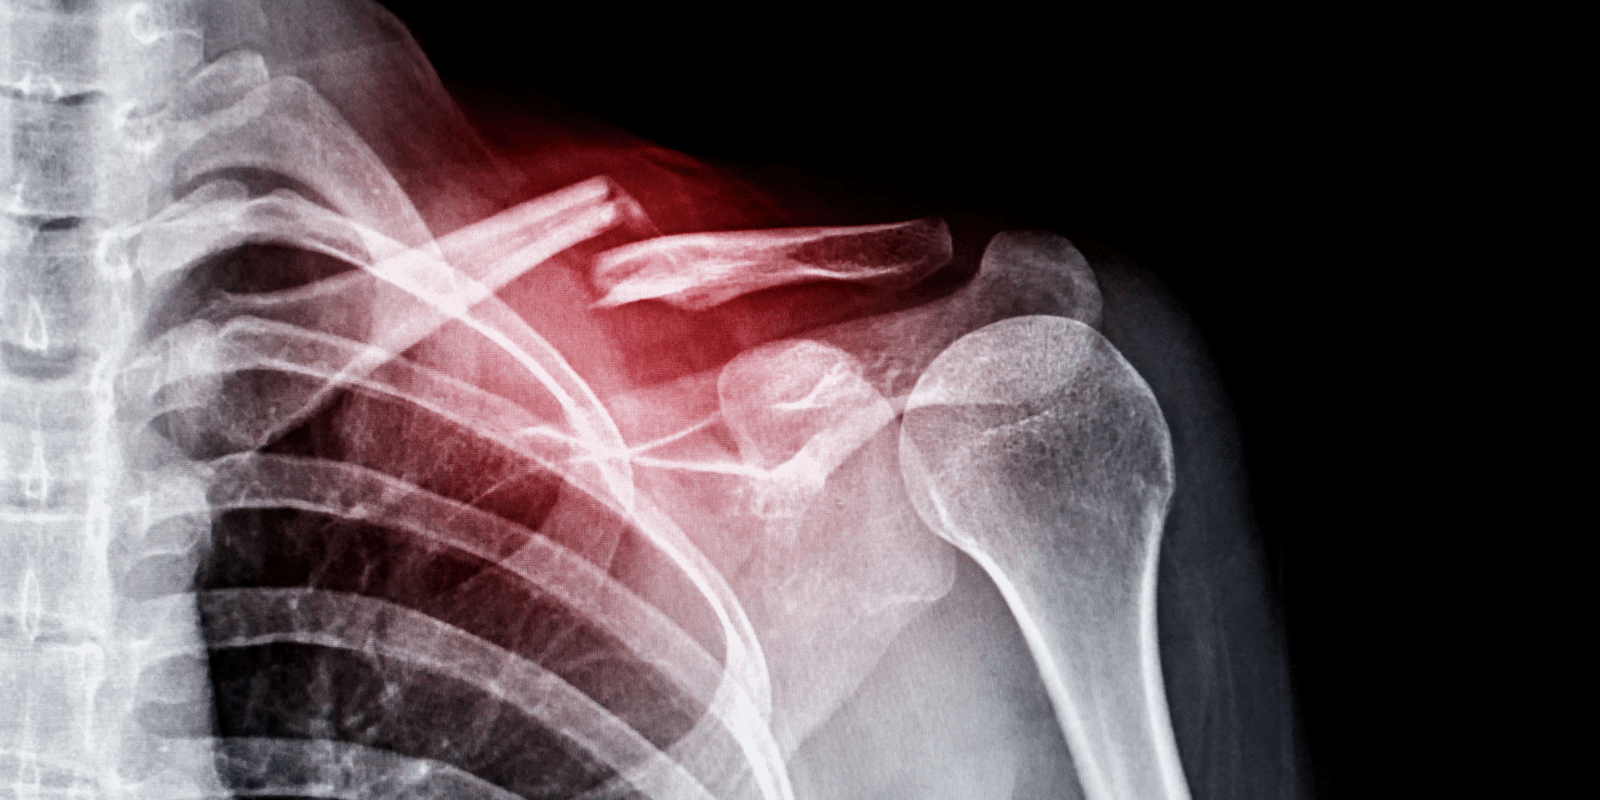

상완골 골절과 입원 기간

상완골 골절은 팔의 긴 뼈인 상완골이 손상되는 경우를 말하며, 이 또한 낙상이나 직접 충격으로 인해 발생할 수 있습니다. 상완골 골절의 경우, 입원 기간은 통상적으로 2주 정도이지만, 상황에 따라 수술이 필요하거나 추가적인 의학적 관리가 필요한 경우 입원 기간이 더 길어질 수 있습니다. 특히 교통사고와 같이 외상이 심한 경우, 추가적인 치료와 관찰이 요구될 수 있으며, 최대 12주까지 입원하는 경우도 있습니다.